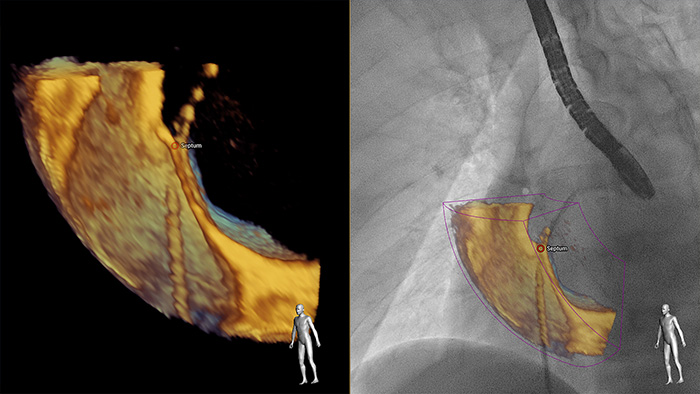

EchoNavigator

EchoNavigator 3D TEE and live X-ray

Greater insight and confidence in finding and treating the problem through SmartFusion. EchoNavigator automatically fuses live 3D TEE and live X-ray in real time so you can intuitively guide your device in the 3D space more quickly.